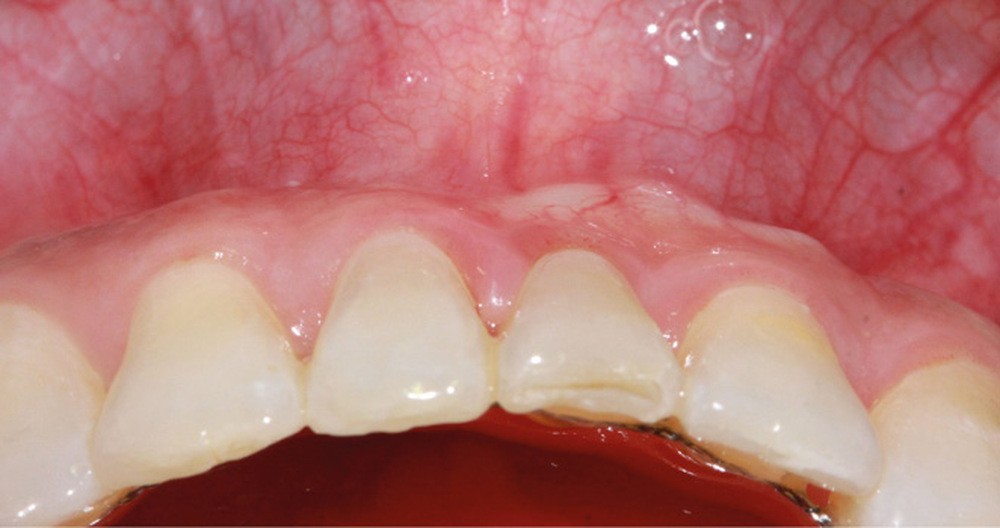

10. Contrôle à un an postchirurgie : environnement parodontal en regard des incisives mandibulaires : vue vestibulaire (a), vue occlusale (b). L’environnement musculaire est toujours pacifié (c). L’hygiène est encore à améliorer.